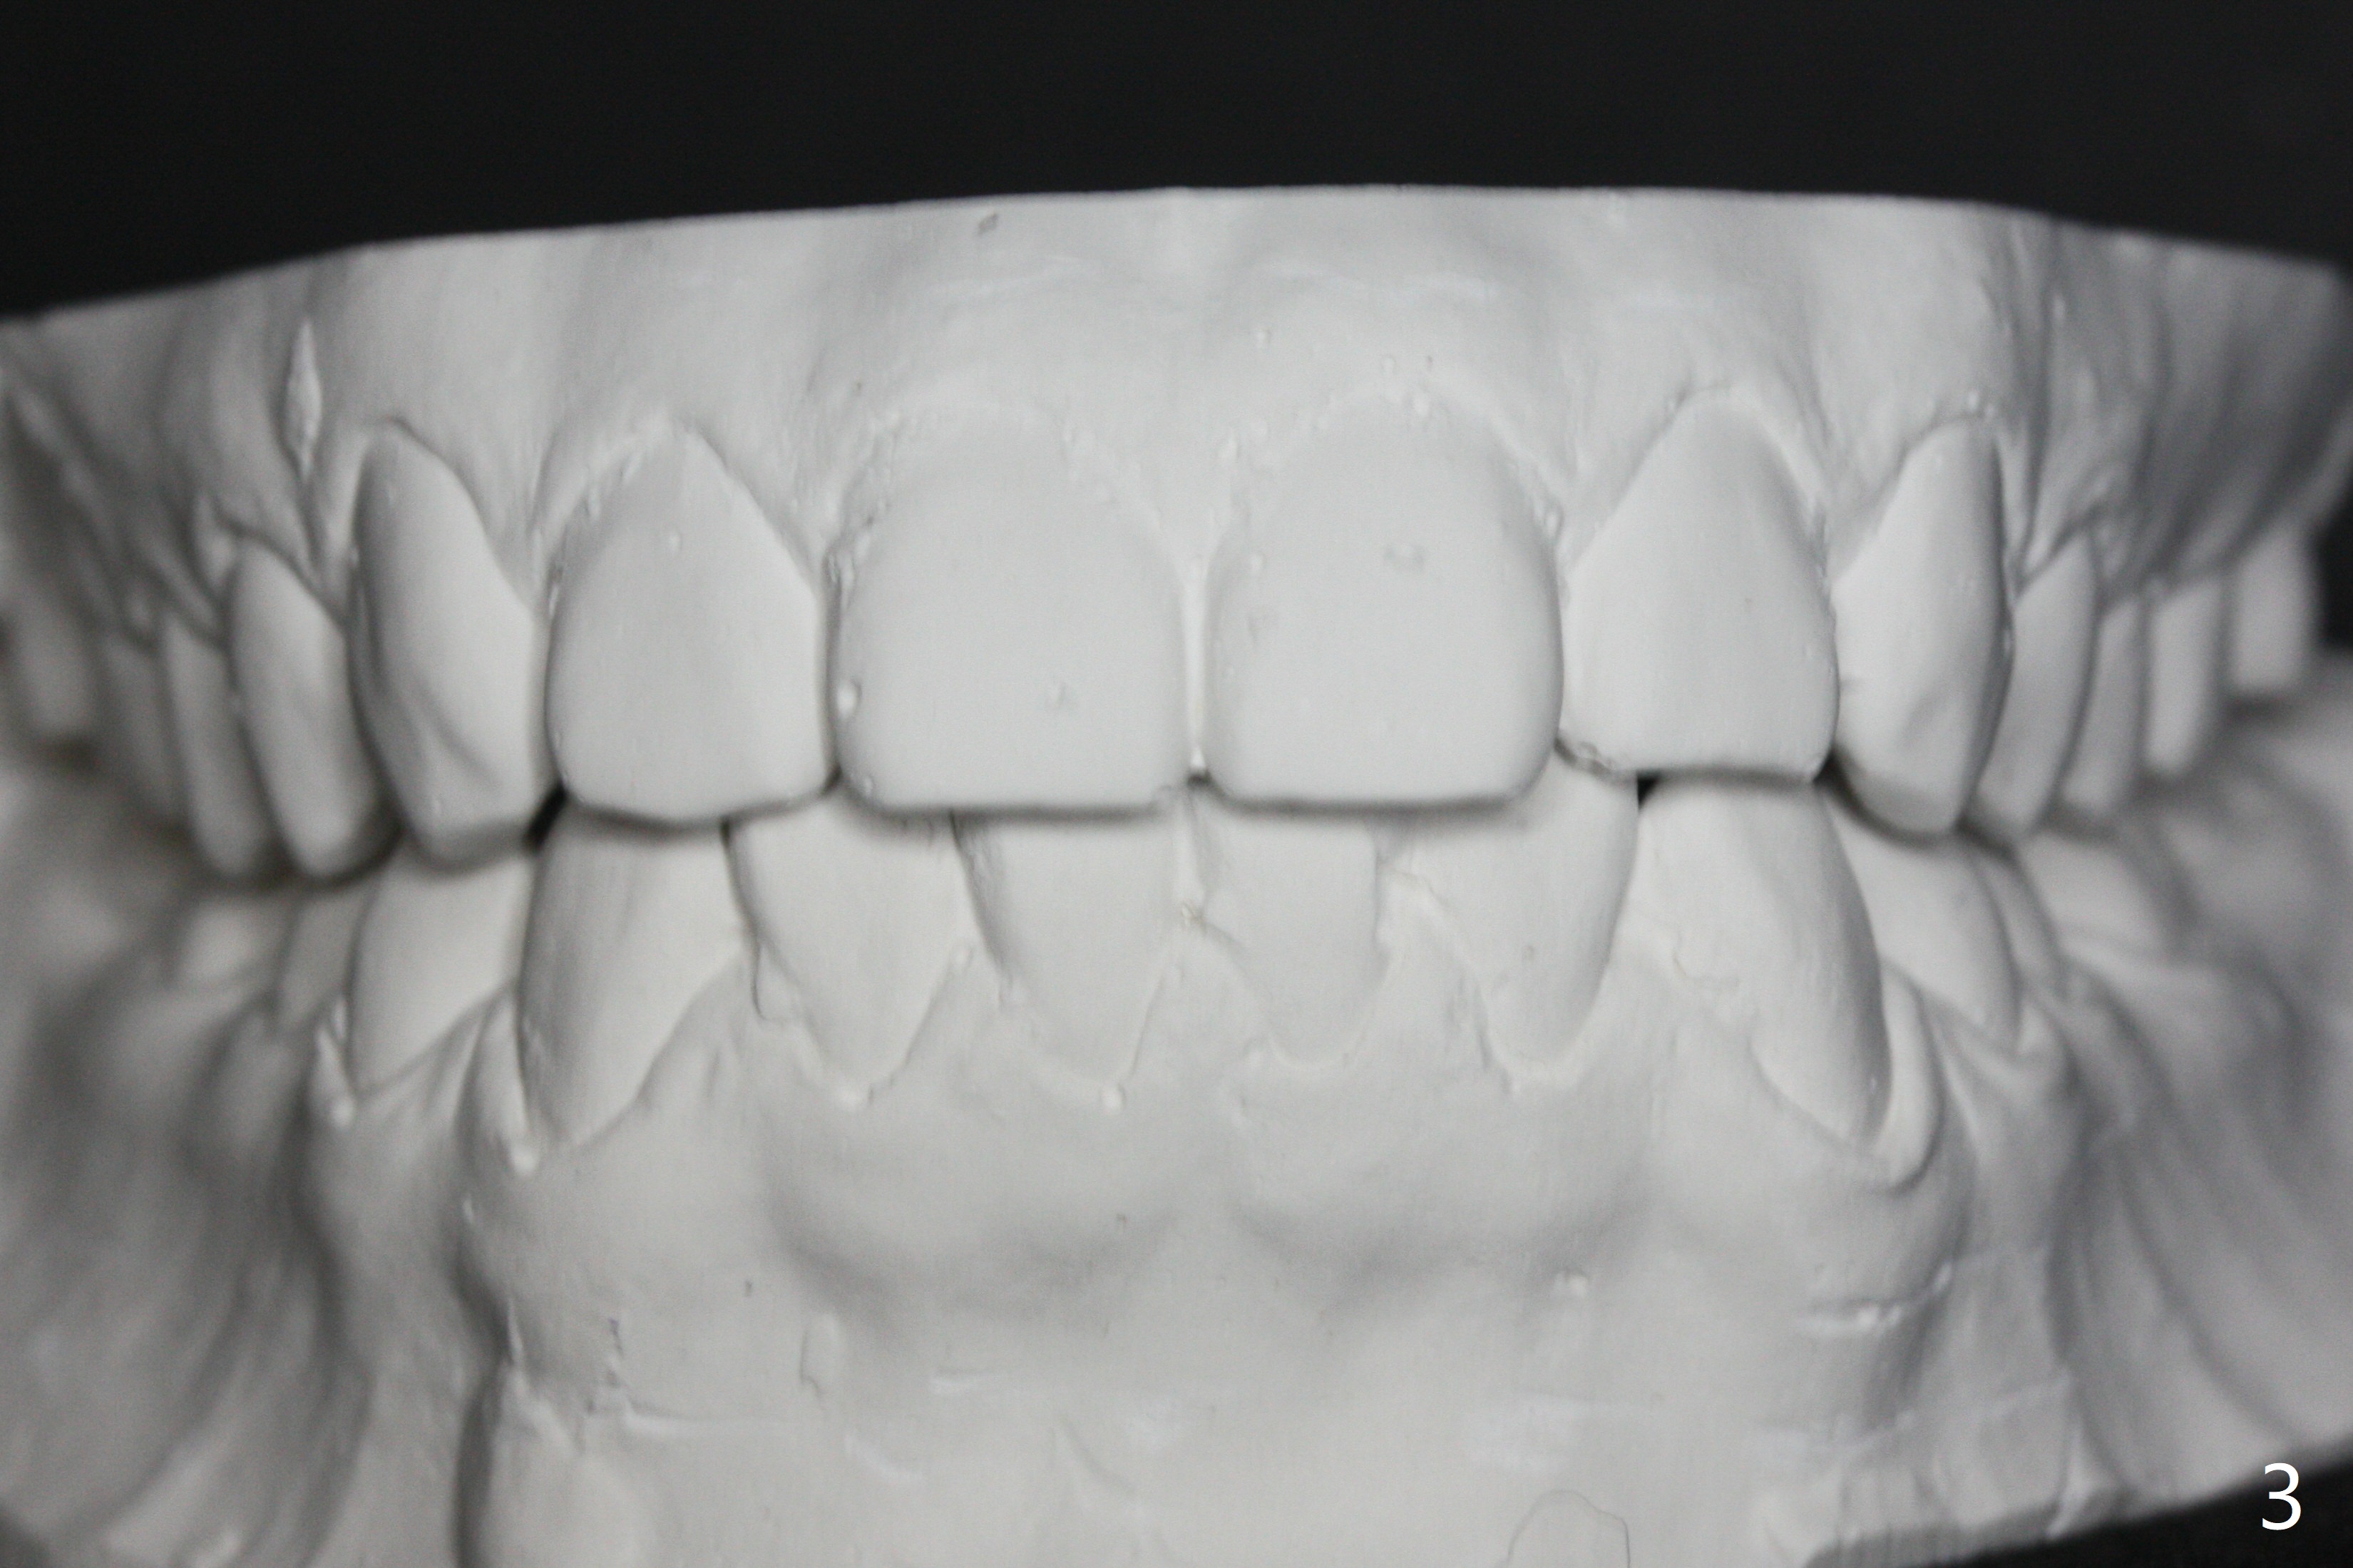

| Pre-op (11 y/o) | Post-op (12 y/o) | Follow Up (14 y/o) |

A 11-year-old man starts orthodontic treatment and finishes in 9 months. Two years later crowding relapses because of loss of suck down retainers. It appears that lingual retainer is necessary.